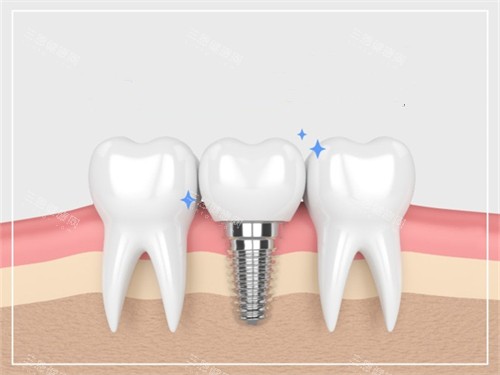

本文将解析乐山英美口腔在种植牙领域的优势,包括医生团队的背景、设备配置的丰富性、2025年价格体系、特色服务项目以及真实患者评价,为有种植牙需求的朋友提供详实的参考信息。

值得一提的是,乐山英美口腔在本地服务已有多年的历史积淀,通过不断引进新技术、新设备,逐步发展成为集种植牙、正畸、美学修复、儿童齿科等为一体的综合性口腔医疗机构。特别是在种植牙领域,医院投入了大量资源,建立了专门的种植中心,为不同需求的患者提供多样化的解决方案。

乐山英美口腔在硬件设备上的投入可谓不遗余力,为种植牙手术的精密性和靠谱性提供了坚实因素。医院引进了国内外比较靠前的口腔锥形束CT(CBCT),能够获取高清晰度的三维影像,更好测量牙槽骨的高度、宽度和密度,识别重要的解剖结构如下牙槽神经、上颌窦等,避免手术中的意外损伤。

智能化技术的应用是乐山英美口腔的一大特色。通过口内扫描仪取代传统的取模方式,不仅提高了舒适度,还能获取更加更好的牙列数据。这些数据与CBCT影像结合,利用正规的种植设计软件,可以在计算机上预先规划种植体的位置、角度和深度,并制作智能化手术导板,实现"所见即所得"的精密种植。